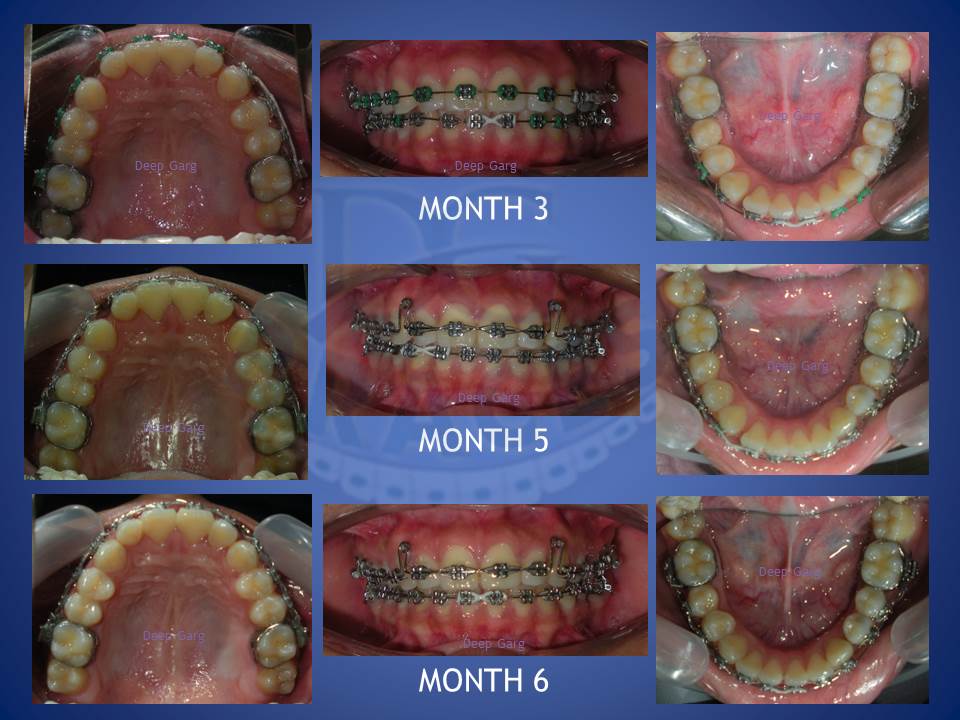

4.Dental spaces are better corrected witht the help of braces in comparison to artificial means like fillings and crowns.